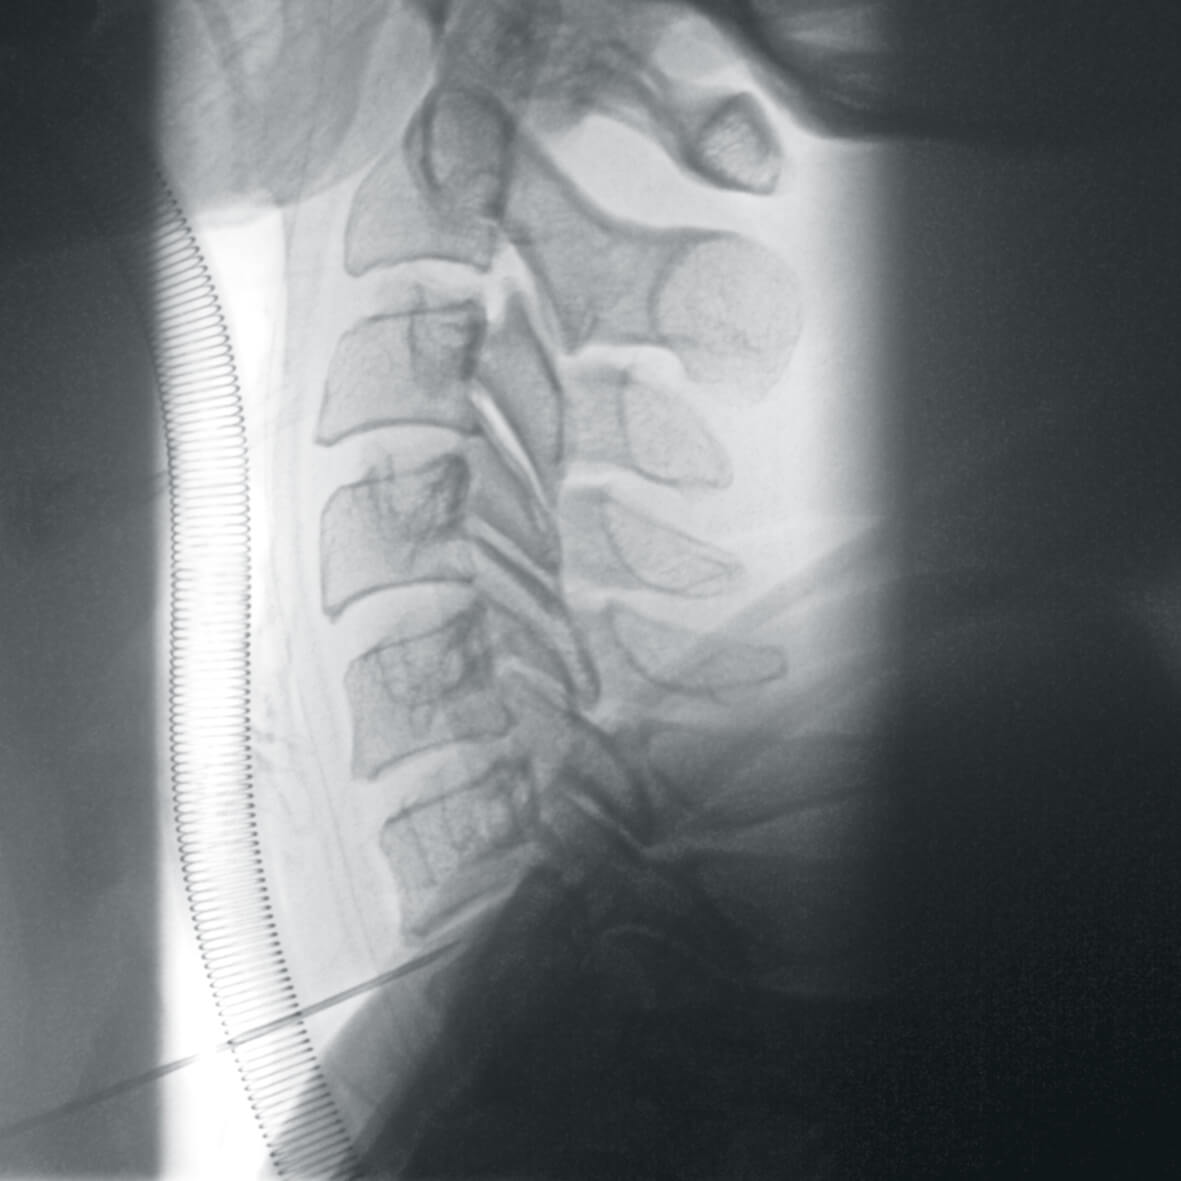

- нейрохирургия,

- вертебрология,

Полное отсутствие искажений снимков в сочетании с высоким динамическим диапазоном широко востребованы как при сложных операциях в нейрохирургии, сосудистой хирургии, инвазивной радиологии, так и в гибридных областях применения, а также в ортопедии, травматологии. В сосудистой хирургии особенно важны высокий динамический диапазон и пространственное разрешение, обеспечивающие детальную визуализацию даже мельчайших сосудов. Специализированное программное обеспечение SmartVascular позволяет проводить настройку системы для васкулярных операций и сосудистой хирургии.

Точная визуализация анатомических деталей, мягких тканей и костных структур обеспечивается за счет светочувствительной матрицы 3kх3k пикселей с высоким динамическим диапазоном.